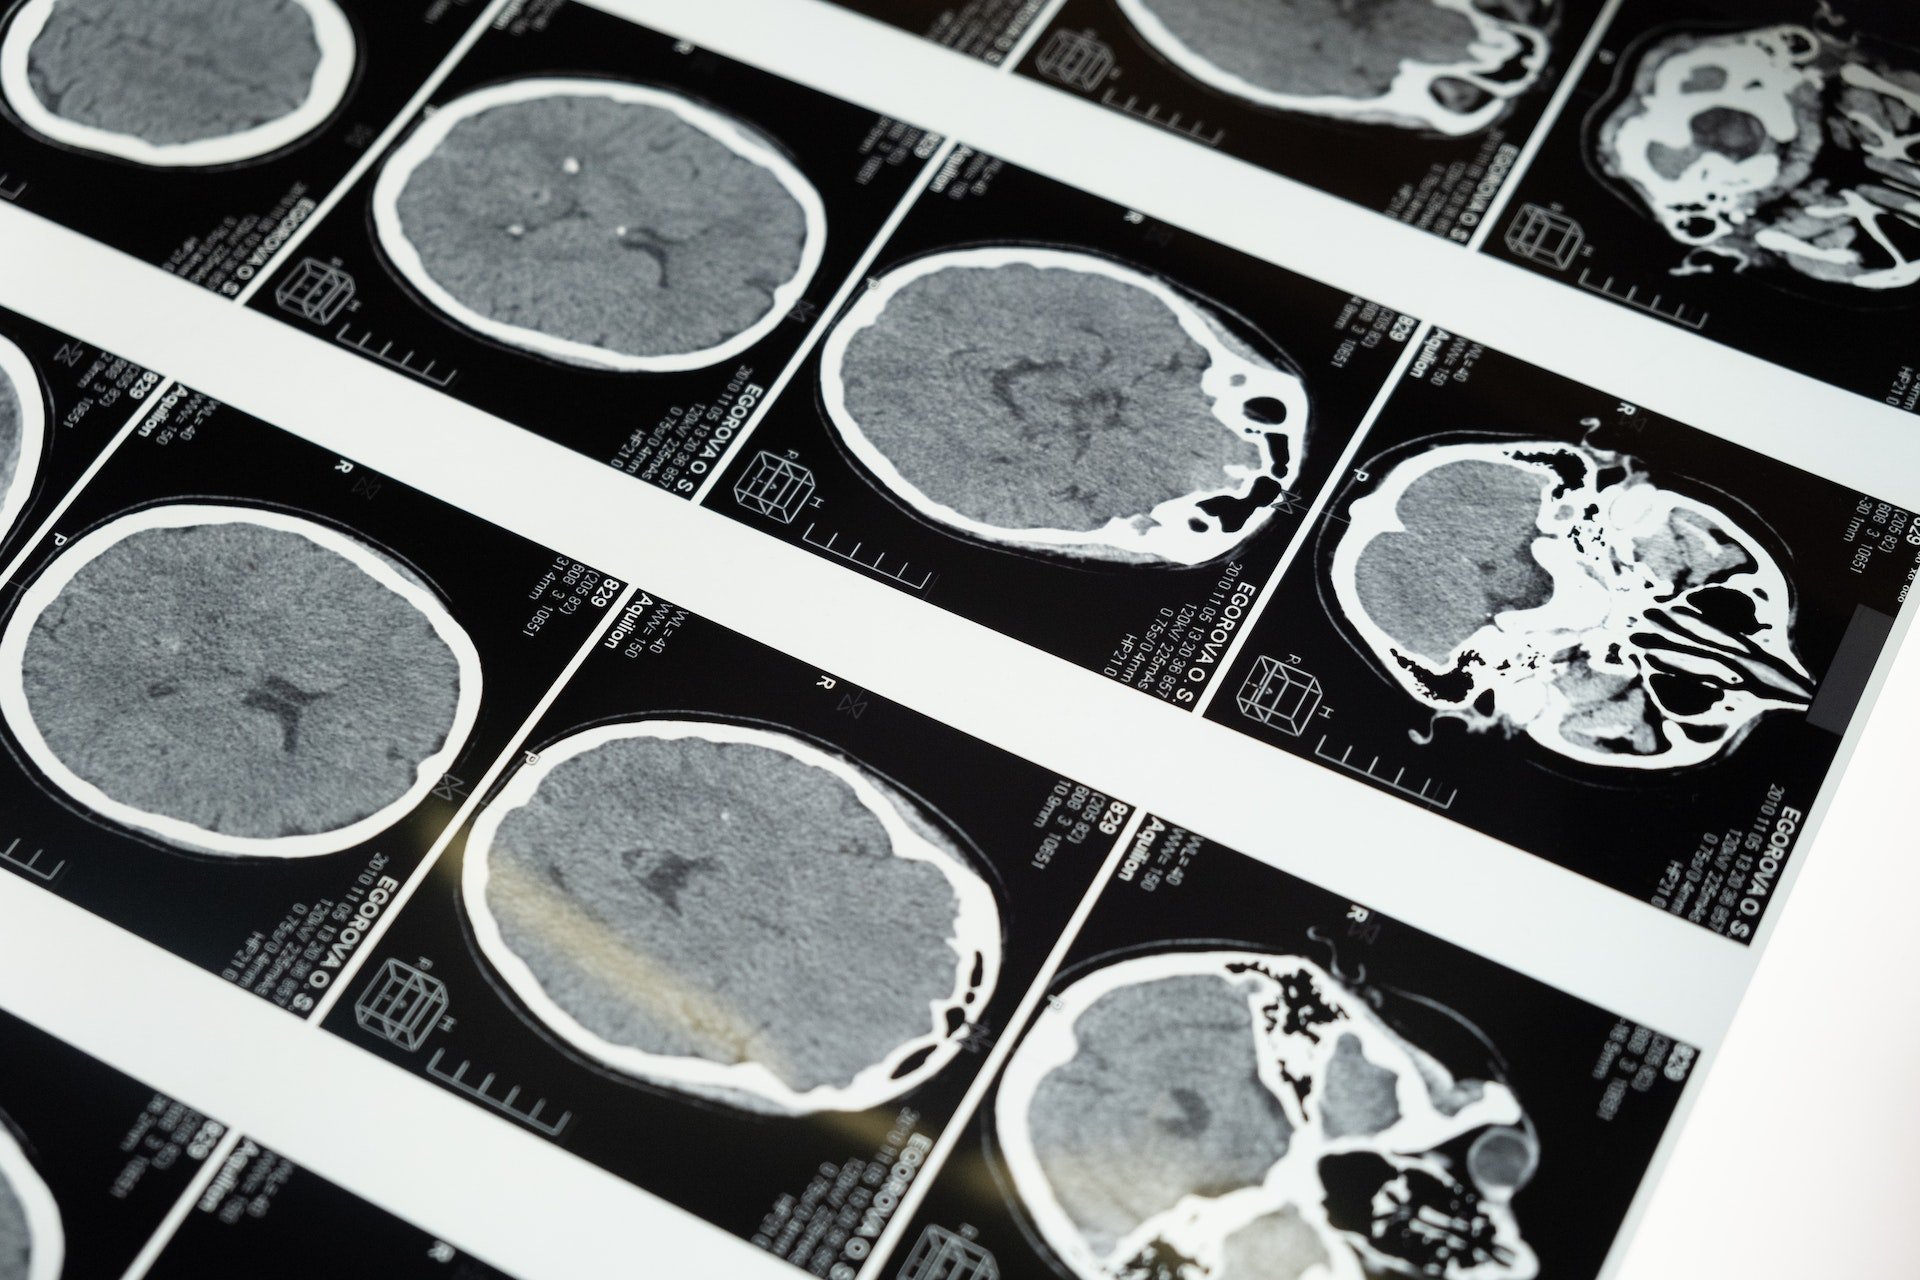

Kanıtlanmış ve hastalara uygulanan spesifik tedavi biçimi olmadığı gibi tanıda özgü test bulunmamaktadır. Bireyde görülen semptomlarla beraber hastalığı doğru teşhis etmek amacıyla uyandırılmış potansiyeller, LP, MR tetkikleri multipl skleroz tanısını destekler niteliktedir. Hastalığa bağlı ölüm meydana gelmez. Multipl skleroz oluşumunun hangi nedenle ortaya çıktığı bilinmemektedir. Genetik veya çevresel olabileceği düşünülmektedir. Tedavide ise ataklar için damar yolundan kortikostreoid ilaç grubundan ilaçlar uygulanır. Bunun yanı sıra kanda bulunan plazma kısmının değiştirilmesi işlemi yapılabilir.